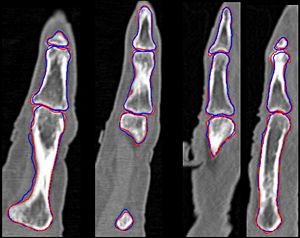

- Segmentation algorithm has been applied to segmentation of the phalanx bones on the index finger

Figures: